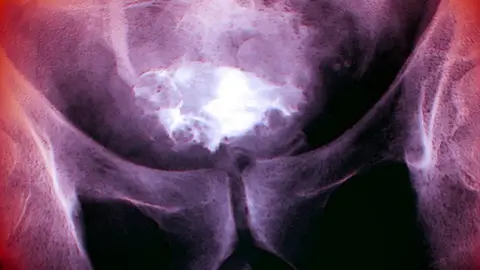

Science Photo LibraryA strain of the common cold virus can infect and kill bladder cancer cells, a small study suggests.

Science Photo LibraryNormally, the tumours in the bladder are "cold" because they do not have immune cells to fight off the cancer.